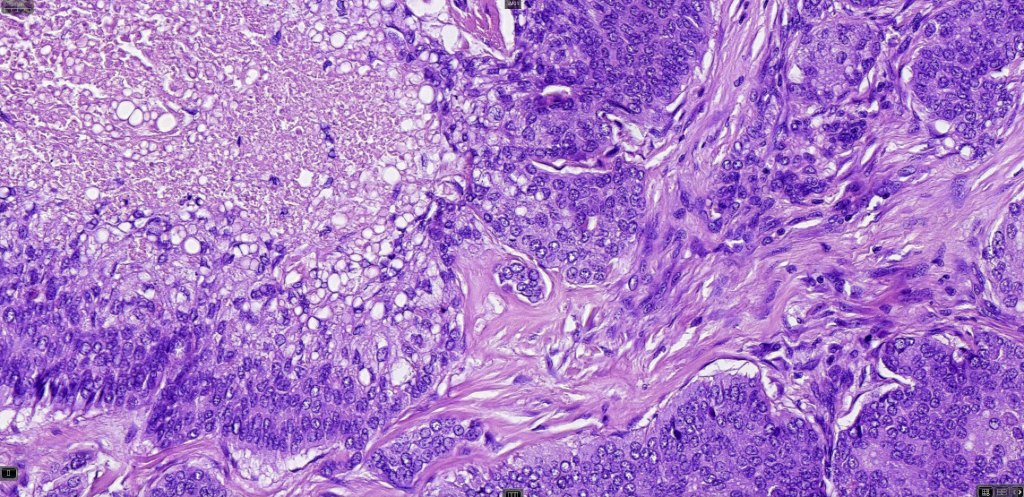

Histological features

•Tumors are composed of an admixture of darkly staining basaloid cells with hyperchromatic or vesicular nuclei and more obvious sebaceous cells with eosinophilic, bubbly, multivacuolated cytoplasm frequently indenting the nucleus (scalloped)

•Often mitoses are numerous and abnormal forms evident

•Focal squamous differentiation with keratinization can be present resulting in confusion with squamous cell carcinoma

•Frozen section-stained tumor cell lipid can be highlighted with Oil Red O

Sebaceous carcinoma from a patient with Muir-Torre syndrome kindly shared by Dr. Antonina Kalmykova.